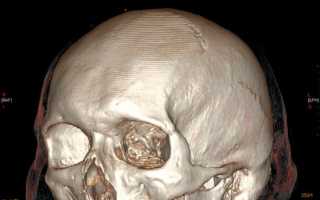

С появлением КТ значение обычной рентгенографии в выявлении переломов черепа значительно уменьшилось, назрел вопрос о пересмотре диагностической тактики при ЧМТ. В настоящее время следует считать правилом, что при наличии соответствующей аппаратуры в первую очередь необходимо проведение компьютерной томографии.

МСКТ является прекрасным методом выявления травматических повреждений, гематом, переломов, ретробульбарного скопления воздуха. КТ и МРТ обладают одинаковой чувствительностью в выявлении орбитальных опухолей: глиома, менингиома, лимфангиома, гемангиома, гемангиопероцитома и др, а также внеконусных образований: опухоли слезной железы, дермоид, лимфома, псевдоопухоли, метастазы, тиреоидная миопатия.

КТ и МРТ обеспечивают хорошую визуализацию турецкого седла. Однако МРТ обладает рядом преимуществ-более хорошее мягкотканое разрешение, недостаток-плохо видит кальцинаты. В свою очередь МСКТ является методом выбора при всех неотложных состояниях с травмами головы.

МСКТ остается методом выбора и особенна эффективна при обызвествлениях, инородных тел, костных структур. Некоторые опухоли нр гемангиома лучше видны при МРТ. При бактериальных поражениях мозга-абсцессах, менингитах,эмпиемах могут возникать трудности диагностики с опухолевым поражением, что требует введения контраста.

Клинические показания:

- травма головного мозга, лицевого черепа с подозрением на внутричерепное или субарахноидальное, субдуральное кровоизлияние, посттравматические последствия

- изменения в костях свода и основания черепа